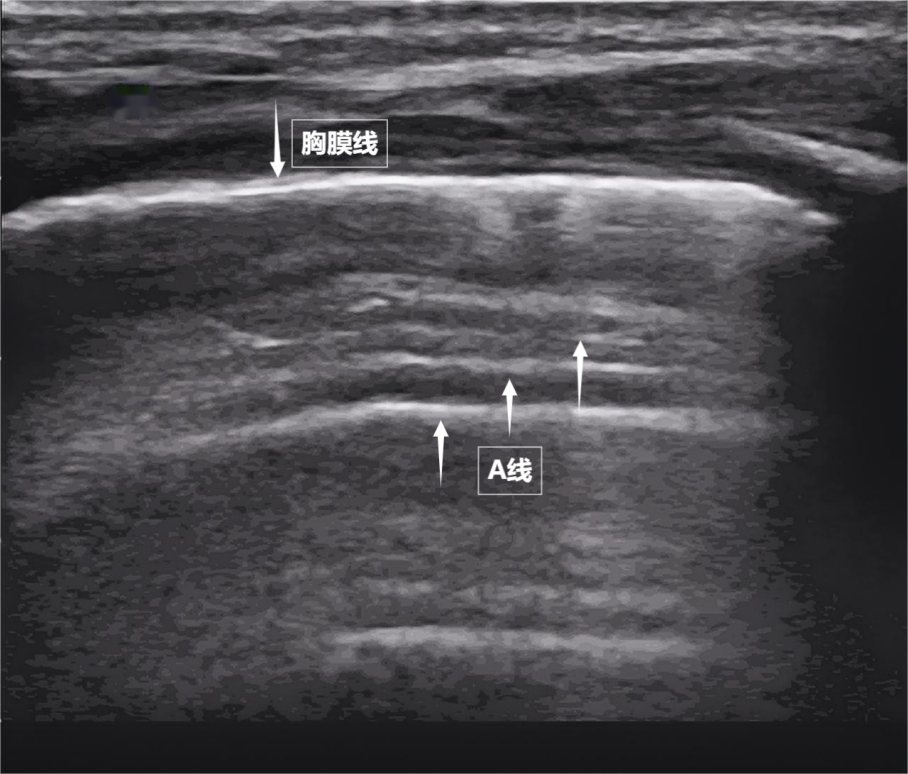

第一景:“海岸线与海浪”——胸膜线与A线当声波穿过胸壁肋骨缝隙,首先会遇到紧贴肺表面的光滑薄膜——壁层胸膜和脏层胸膜。两者紧密相贴,中间没有多余的气体或液体。它们在屏幕上呈现为一条明亮、光滑的水平线,共同构成了胸膜线。这条线就是肺的“海岸线”。在它的下方,由于肺泡内大量气体对声波的强烈反射,会出现一系列与胸膜线平行的、等间距的、重复出现的明亮平行线,像海浪般不断向屏幕深处延伸,这就是A线(见下图)。A线是正常含气肺部的典型标志。它的存在直接提示肺表面含气充足,胸膜腔内无异常积液或气体。

图为正常新生儿肺部超声表现